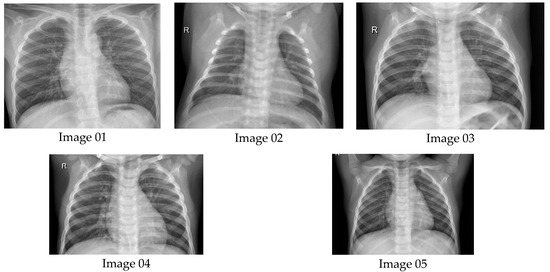

6.1. Results from Lung Radiographs

- Kaggle. Chest X-ray Images (Pneumonia). 10 February 2018. Available online: https://www.kaggle.com/datasets/paultimothymooney/chest-xray-pneumonia (accessed on 24 August 2023).